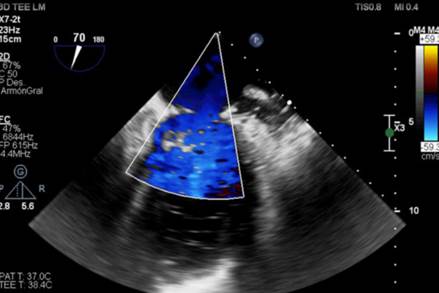

Con diagnóstico positivo de endocarditis infecciosa sobre válvula nativa mitral a S. aureus con insuficiencia mitral severa, se decide continuar con tratamiento quirúrgico. En la exploración intraoperatoria se observó una válvula mitral con degeneración mixomatosa del velo posterior y con rotura de varias cuerdas a nivel de festones P2 y P3. Se constató una pequeña vegetación a nivel de sitio de inserción de cuerda tendínea sobre músculo papilar posterior. Se llevó a cabo una plastia valvular mitral con colocación de tres neocuerdas (Chord-X) desde el músculo papilar posteromedial al sitio de rotura cordal. Como luego de realizar dicha reparación la válvula permanecía insuficiente frente a las maniobras hidráulicas, se decidió realizar resección cuadrangular del segmento valvular insuficiente y reconstrucción de este. Se implantó, además, un anillo mitral semirrígido de 34 mm. El ecocardiograma transesofágico intraoperatorio evidenció una válvula mitral estable, normofuncionante, sin fugas y con gradientes anterógrados adecuados (figura 3). El paciente evolucionó de manera favorable, sin complicaciones. Se otorgó alta precoz y continuó con tratamiento antibiótico ambulatorio. El ecocardiograma transtorácico de control evidenció una plastia mitral exitosa, con reducción de las dimensiones diastólicas del ventrículo izquierdo.